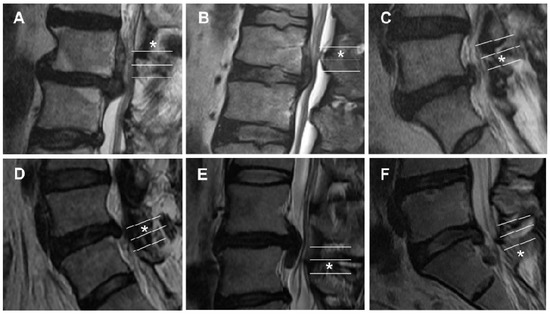

A New Grading System for Migrated Lumbar Disc Herniation on Sagittal Magnetic Resonance Imaging: An Agreement Study

by Yong Ahn, Ji-Eun Kim, Byung-Rhae Yoo and Yu-Mi Jeong

J. Clin. Med. 2022, 11(7), 1750; https://doi.org/10.3390/jcm11071750 - 22 Mar 2022

Cited by 12 | Viewed by 4604

Understanding the degree of disc migration is essential in order to diagnose, treat, and assess the prognosis of migrated lumbar disc herniation (LDH). Based on anatomical configuration, we developed a simple six-level grading system for migrated lumbar disc herniation. We aimed to evaluate [...] Read more.

Understanding the degree of disc migration is essential in order to diagnose, treat, and assess the prognosis of migrated lumbar disc herniation (LDH). Based on anatomical configuration, we developed a simple six-level grading system for migrated lumbar disc herniation. We aimed to evaluate whether the new grading system was reliable and could replace the previous grading system. We selected 101 cases from our database. Two independent raters evaluated the magnetic resonance images using each grading system. Interobserver, intraobserver, and inter-grading system agreements were assessed using kappa statistics. The most common migration pattern was low-grade inferior migration. Interobserver agreements between the two readers showed substantial agreement in the first and second assessments (k = 0.753 and 0.756, respectively). The intraobserver agreement of reader 1 revealed substantial agreement (k = 0.733), while that of reader 2 revealed almost perfect agreement (k = 0.829). The strengths of the agreements of the new grading system were higher than those of the Lee-Kim grading system. The two grading systems agreed almost perfectly for most measurements. The new grading system was reliable and feasible to determine migrated LDH grade. It allowed for a more intuitive, objective measurement and helped select surgical options. Full article

(This article belongs to the Section Clinical Neurology)

Show Figures

Figure 1